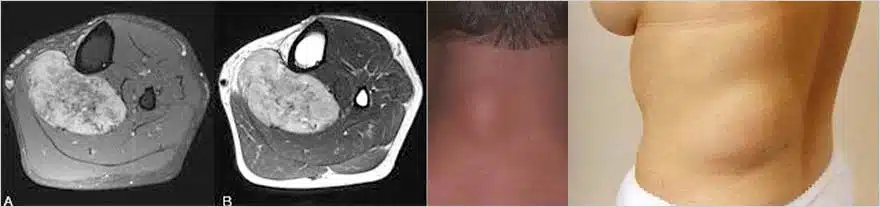

Σπανιότερα, μπορεί τα λιπώματα να εμφανιστούν σε βαθύτερα τοιχωματικά στρώματα, πχ ενδομυϊκά ή και ενδοκοιλιακά κλπ.

Τότε μπορεί η διάγνωση να απαιτεί την διενέργεια μαγνητικής τομογραφίας και η επέμβαση να είναι πολυπλοκότερη.